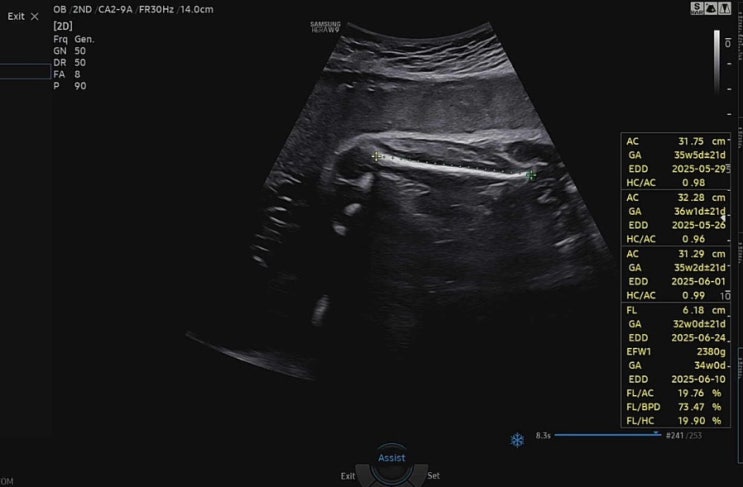

25.04.07 어제 점심 이후로 소화가 안돼서 좀 힘들었는데 결국은 단단히 체했다ㅠ 자궁경부길이는 다시 2.2...